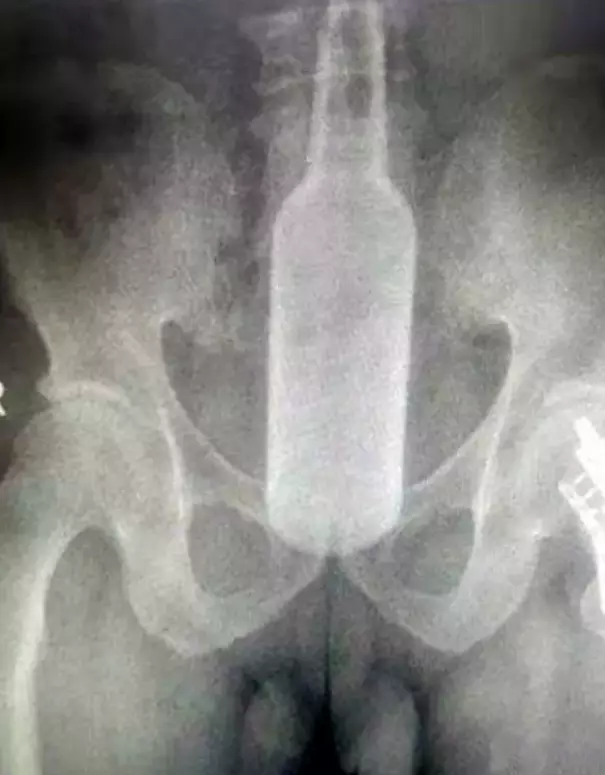

Las imágenes de rayos X muestran cómo quedó el vaso de cerveza de 6 casi centímetros en el recto del paciente.

Pero este tipo de incidentes ocurren más de lo que esperarías. Justo en noviembre pasado, otro hombre chino fue al Hospital después de que una botella de 17,7 cm de largo se atascara en su trasero.

El hombre de 60 años dijo que había estado usando la botella para rascarse la espalda cuando accidentalmente perdió el control del artículo.

El doctor Lin Jun dijo a los medios locales: “El paciente me dijo: ‘Me duele el abdomen. Hay algo adentro. No puedo hacer caca ni tirarme un pedo‘. Toda la botella de vidrio estaba dentro de su recto. Podía sentir la botella debajo de su abdomen.

“Según le picaba el ano. Se excuso diciendo: “Estaba muy incómodo, así que compré una botella de agua de Florida y comencé a rascarme la picazón. Entonces la botella subió accidentalmente por mi recto”.

Los cirujanos retiraron el frasco del recto del paciente, atando un alambre alrededor del frasco y tirando de él suavemente.